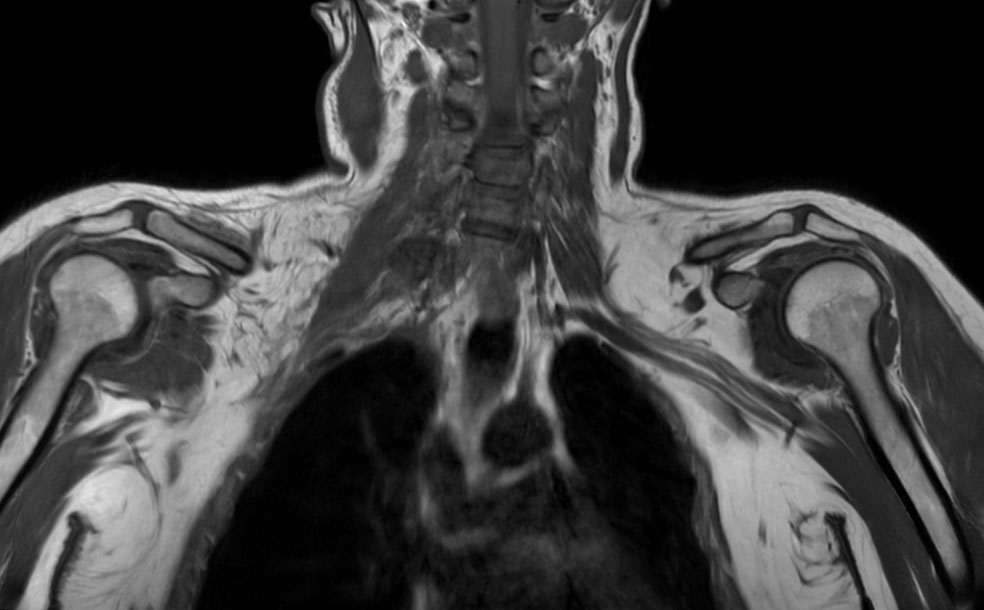

Coronal T1w TSE